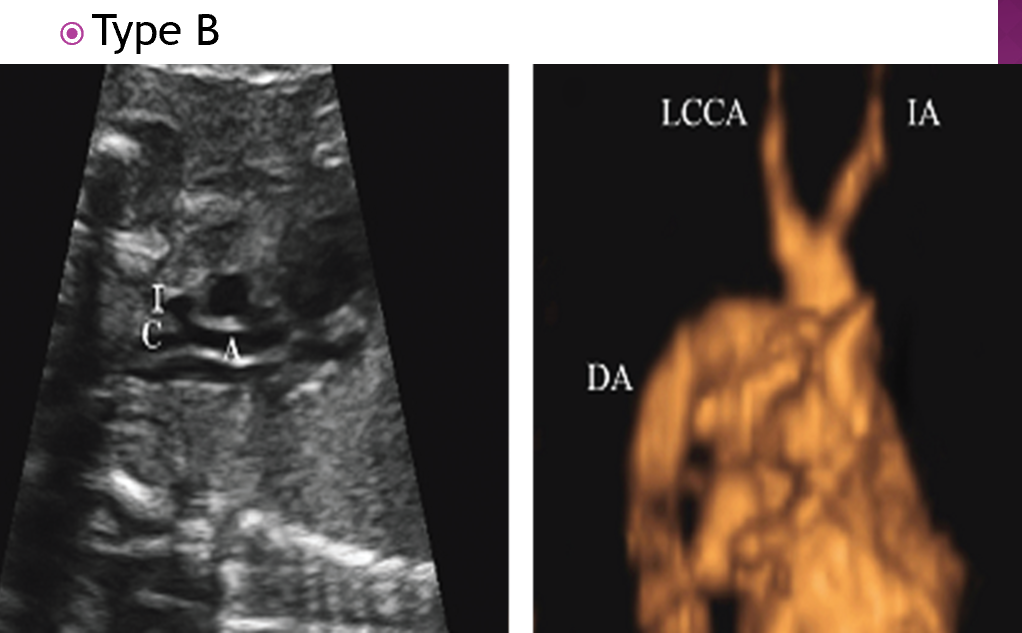

in type B IAA where is the interruption?

between left subclavian and the LCCA

type B IAA is associated with what syndrome?

50% association with digeorge syndrome

how does type B present clinically?

right arm BP > LT arm

what is type C IAA?

when interruption occurs proximal to the LCCA between the brachiocephaic art

which type of IAA is most common?

type b